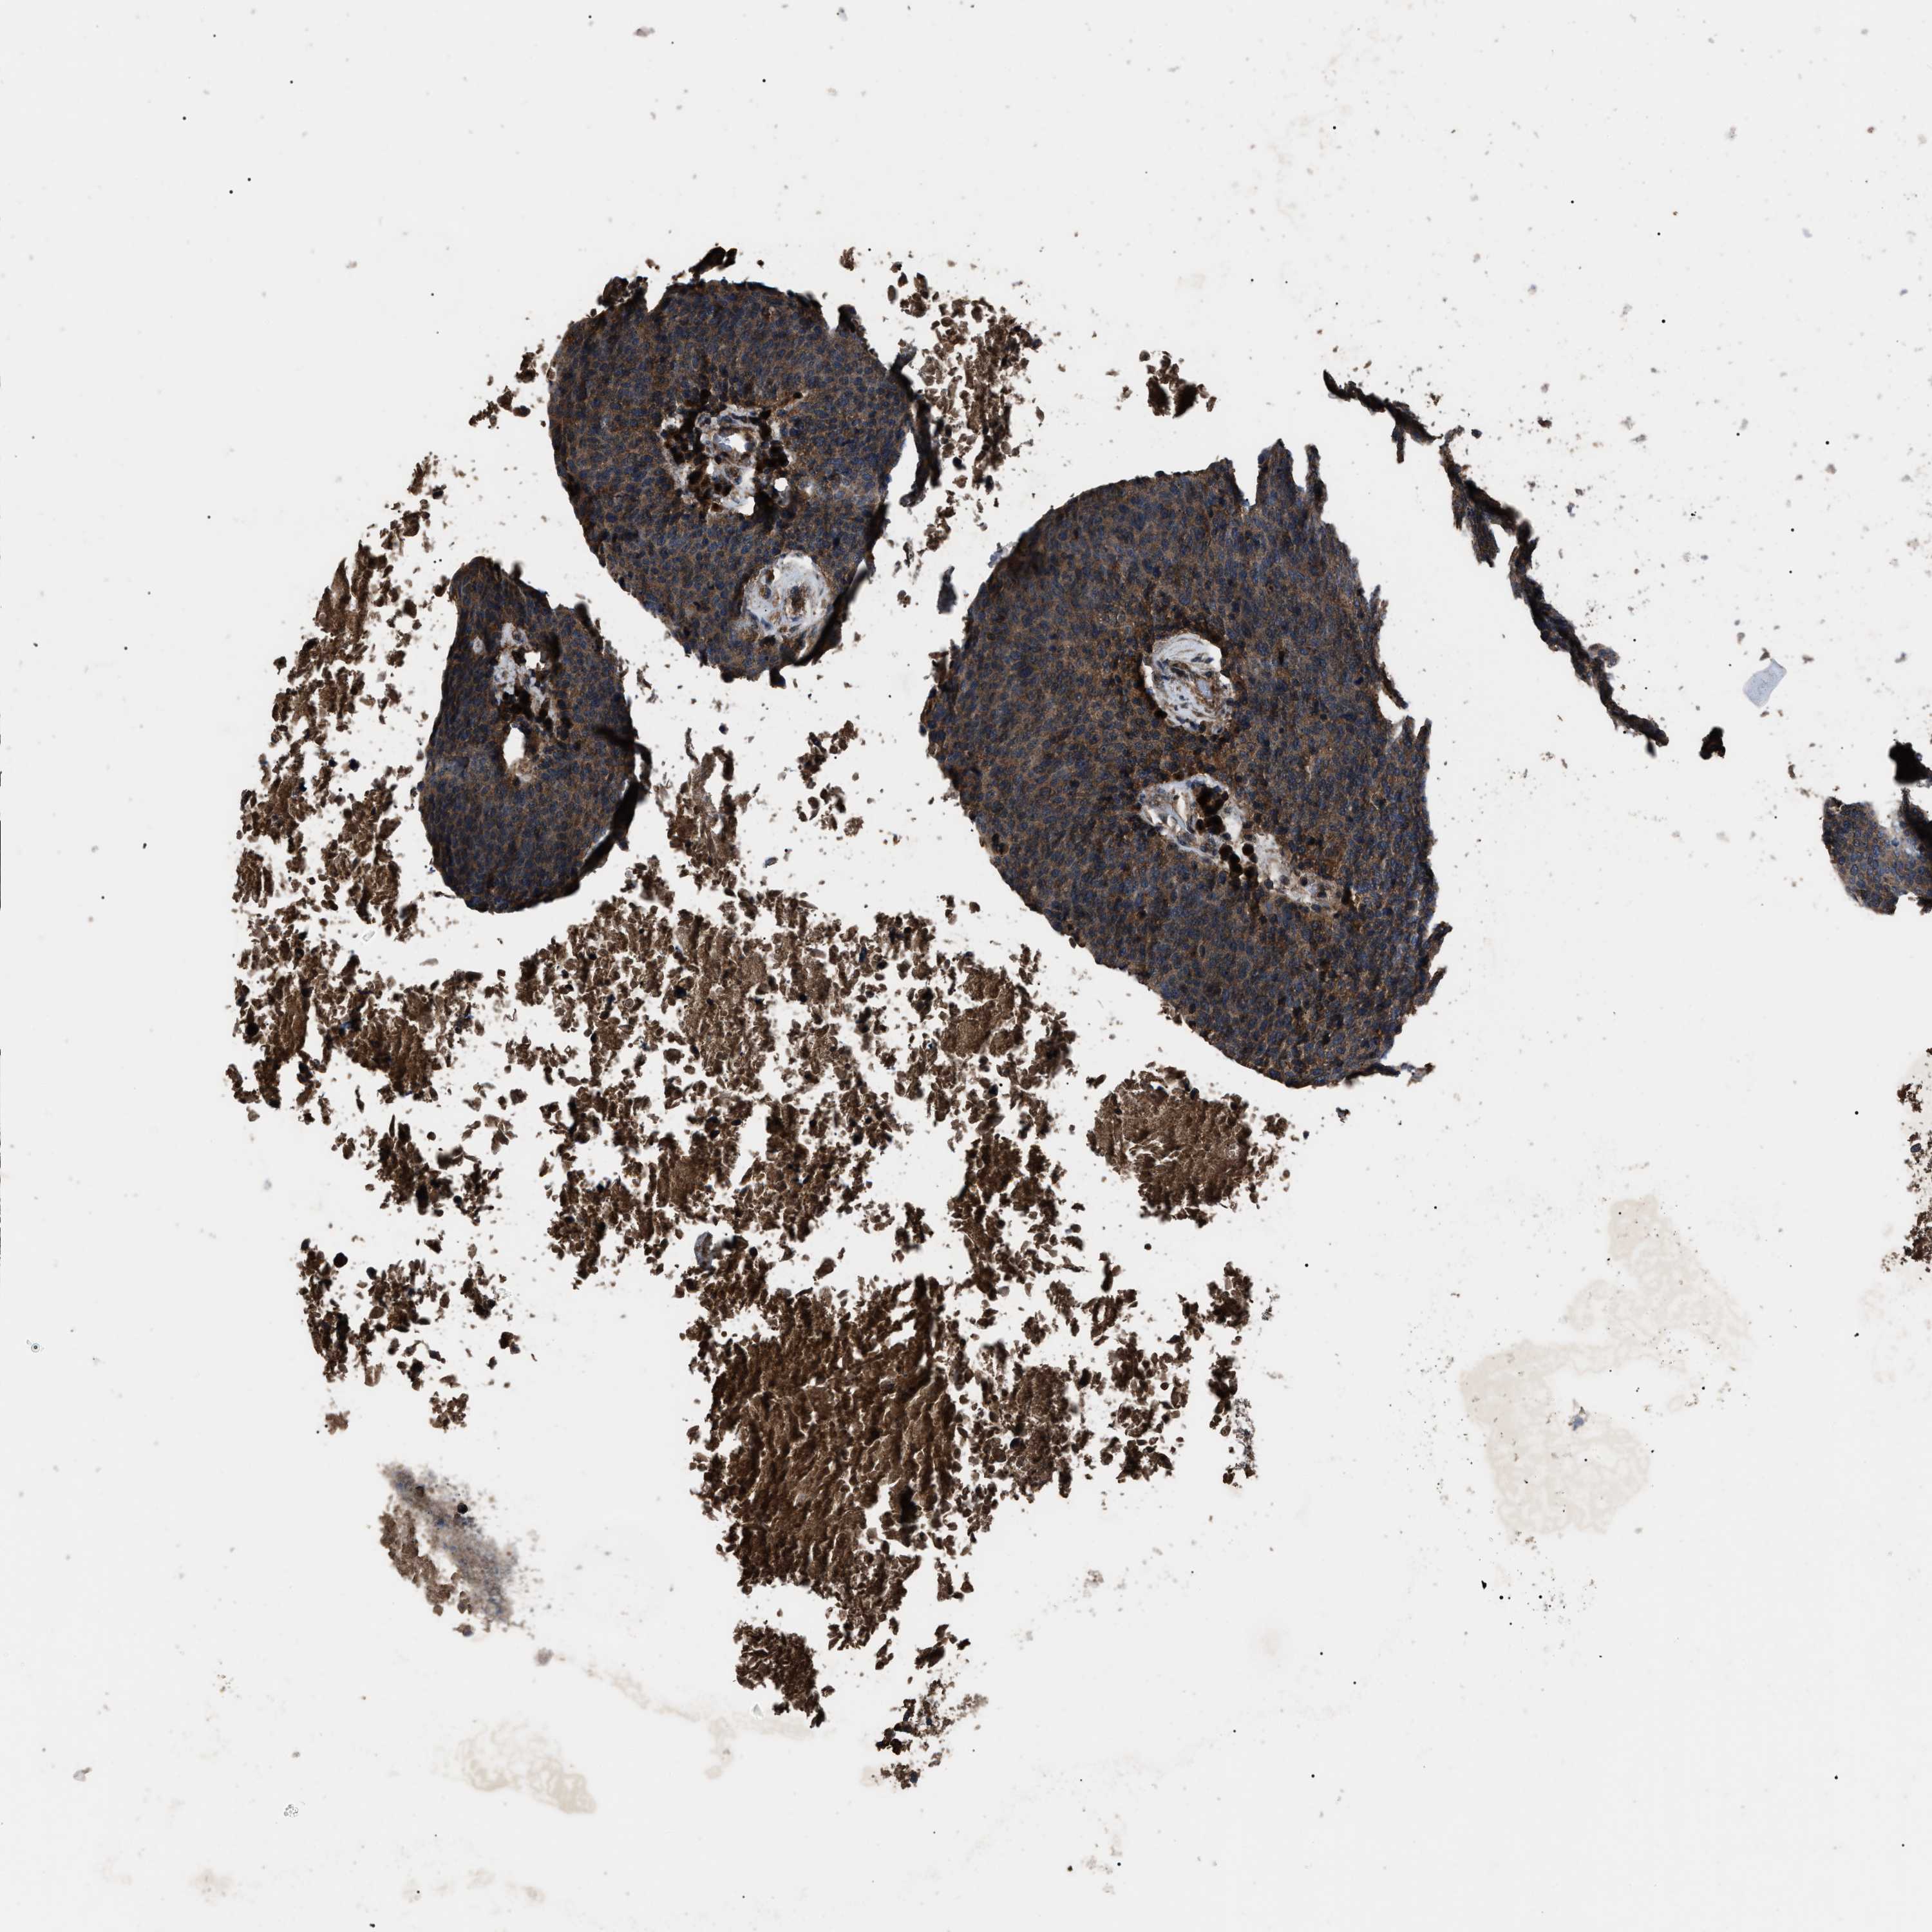

HEAD AND NECK CANCER - Protein expressioni

A mouse-over function shows sample information and annotation data. Click on an image to view it in a full screen mode. Samples can be filtered based on level of antibody staining by selecting one or several of the following categories: high, medium, low and not detected. The assay and annotation is described here.

Antibody stainingi

Antibody staining in the annotated cell types in the current human tissue is reported as not detected, low, medium, or high, based on conventional immunohistochemistry profiling in selected tissues. This score is based on the combination of the staining intensity and fraction of stained cells.

Each image is clickable and will lead to virtual microscopy that enables deeper exploration of all samples and also displays staining intensity scores, fraction scores and subcellular localization as well as patient and tissue information for each sample.

Antibody HPA018955

Antibody HPA021123

Staining

High

Medium

Low

Not detected

Intensity

Strong

Moderate

Weak

Negative

Quantity

>75%

75%-25%

<25%

None

Location

Nuclear

Cytoplasmic/membranous

Cytoplasmic/membranous,nuclear

Squamous cell carcinoma, NOS

Squamous cell carcinoma, metastatic, NOS

Adenocarcinoma, NOS